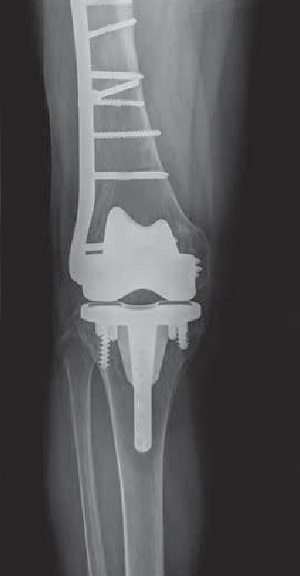

Periprosthetic knee fracture fixation is a procedure performed to stabilize a fracture that occurs in the bone present around a knee prosthesis. The fracture may involve the lower part of the thighbone (femur), the kneecap (patella) or the upper part of the shinbone (tibia).

Revision Prosthesis: When there is a loosening of the prosthesis, the whole implant will usually have to be surgically removed and replaced with a hinged knee prosthesis, which can be considered a salvage device that provides better stability to the knee.